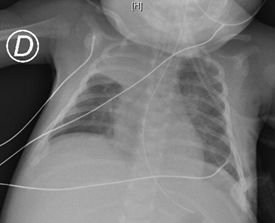

A detailed infectious study was completed, which showed negative microbiological findings (blood culture, control urine culture, cerebrospinal fluid culture, stool culture, conjunctival exudate culture, nasopharyngeal culture, bronchial aspirate culture), with negative serology (syphilis, HIV, EBV, CMV, Herpes simplex 1 and 2, VZV). Imaging tests (chest X-ray (Figure 2), abdominal, transfontanellar, thoracic and cervical ultrasound) revealed no pathological findings.

Figure 2 Increased density with retraction of the right upper lobe fissure in association with atelectasis.